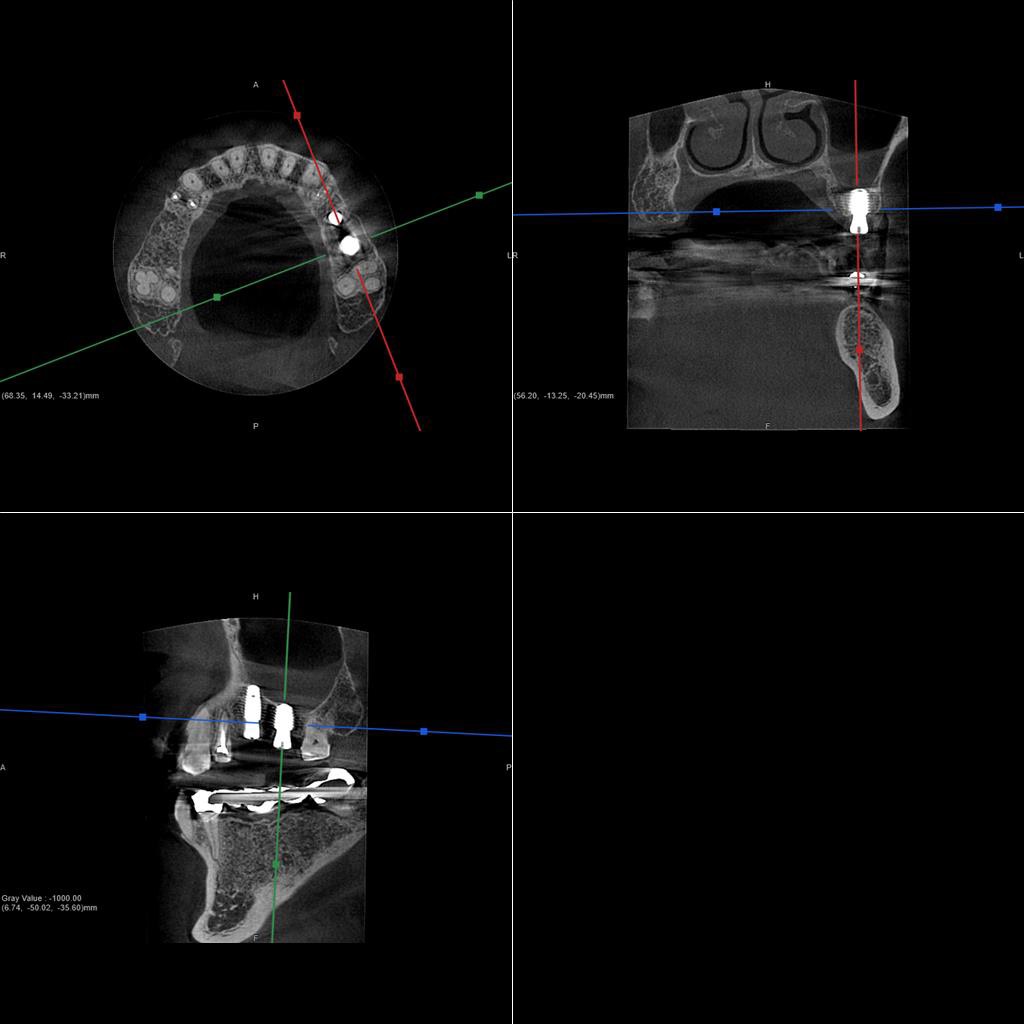

50代、男性、左上に違和感があることを主訴に来院され、インプラント治療を行いました。

| 診断結果 | 左上5番歯根破折 |

| 治療内容 | 抜歯即時インプラント |